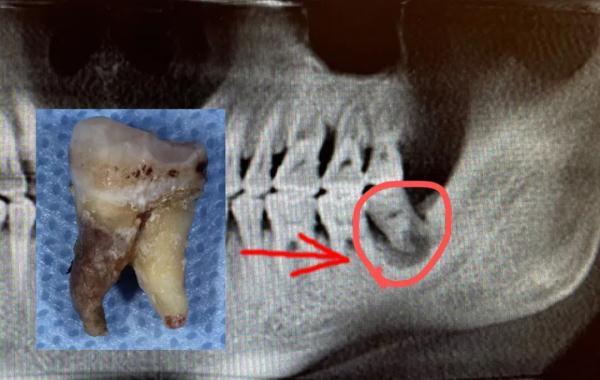

陳申國(guó)說(shuō),這么嚴(yán)重的感染,一般要兩個(gè)星期才能恢復(fù),蔣先生的身體確實(shí)好,才一個(gè)多星期,病灶處的膿液已經(jīng)排得差不多了,可以拔除那顆病牙了。

問(wèn)題牙齒